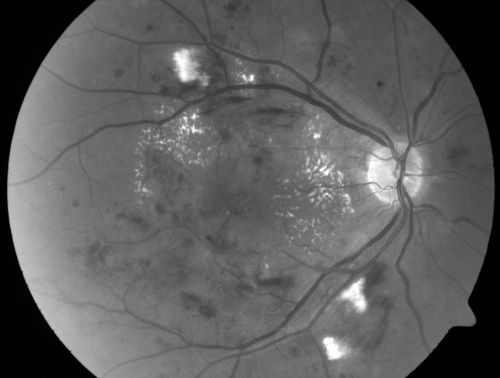

Diabetic Patient with Macular Edema and Blood Pressure 200/95

49-year-old decreasing vision over the last year. OD is 20/80, OS 20/80. blood pressure which was 200/95.

Hypertensive Retinopathy in a Diabetic

macular edema

cotton wool spots

diabetic

hypertensive